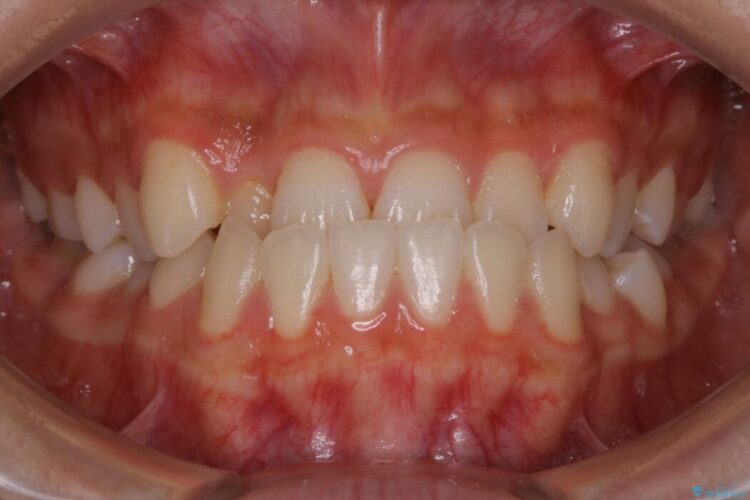

下の歯が上の歯より前に出ている受け口と前歯のガタガタ(叢生)について治療したいとのことで来院されました。

詳しく検査したところ、上顎の歯が舌側に倒れこんでしまっていることや歯列のガタガタなどにより口を閉じた時に上下の前歯の先端が接触してしまっていました。

更に深く噛もうと力を入れると、下顎が前方に突き出して前歯が当たらないように噛んでしまう機能性の反対咬合という診断となりました。

正常な噛み合わせ位置へと改善したことにより奥歯で噛みしめることができ、加えて見た目も受け口から変わって大変ご満足いただけました。